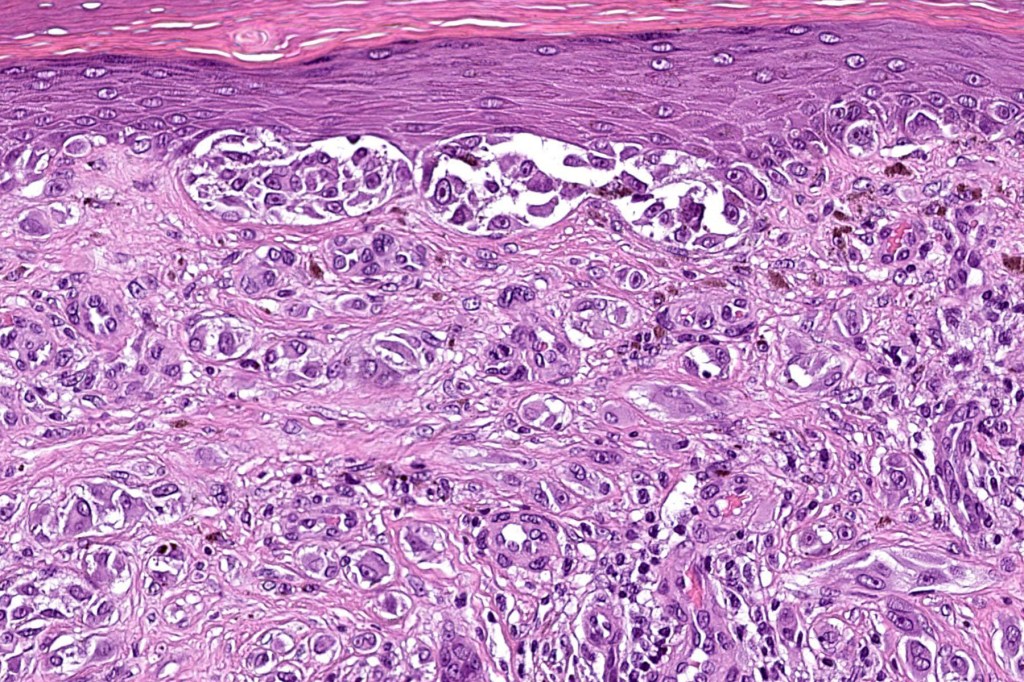

Histological features

•May show effacement/consumption of epidermis or ulceration

•Large nodules which often show impaired maturation

•Loss of gradient with HMB45 and Ki67

•>20% Ki67 expression